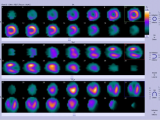

12月7日,国家医疗保障局发布《国家基本医疗保险、工伤保险和生育保险药品目录(2025年)》,锝[99mTc]替曲膦注射液正式纳入2025年国家医保目录,成为国内首个通过国谈进入国家医保目录的诊断类放射性药品。此前,东诚药业公告称,公司全资子公司安迪科的锝[99mTc]替曲膦注射液产品被纳入《国家基本医疗保险、生育保险和工伤保险药品目录(2025年)》,这将提高患者对SPECT-MPI检查的可及性,促进冠状动脉疾病诊疗精准化。中华医学会核医学分会前任主... 2025-12-10 放射性药物